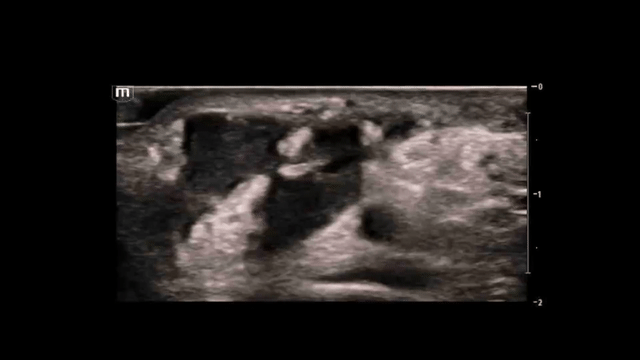

This was our initial view of the right wrist on ultrasound.

• The radial artery (circled) is visualized at a depth of ~1.3 cm just to the right of the midline of the image.

• Sliding the probe superiorly and inferiorly revealed a well circumscribed, complex, hypoechoic structure present just lateral (to the left) of the radial artery.